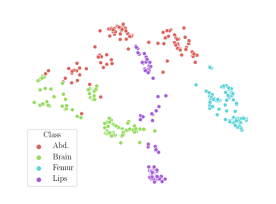

We compare the -distance of categorical features and domain features. Fig. 5 (a) shows that domain difference is higher in domain features than in categorical features. This indicates that domain features contain more domain information whereas categorical features are more domain-invariant. Fig. 6 shows the t-SNE plot of categorical features in both domains for MIDNet. From Fig. 6 (a), we observe that the categorical features learned by MIDNet enable the anatomical classification. Fig. 6 (b) shows that the learned categorical features are domain-invariant.

In addition, we utilize t-SNE plots for feature visualization in Fig. 10. Comparing Fig. 10 (a) and Fig. 10 (b), we observe that with mutual information disentanglement, (1) samples from the same category are more tightly clustered (see the top row) and (2) the source domain and the target domain are overlap more (see the bottom row). This indicates that mutual information disentanglement is important for learning categorical-focused and domain-invariant features. Fig. 10 (a), (c)-(d) show that the proposed method outperforms other state-of-the-art methods for learning category-discriminative and domain-invariant features, especially for unseen categories in the target domain (e.g., (a) vs. (d)).